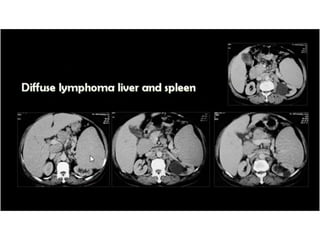

This document discusses the spleen and causes of splenomegaly (enlarged spleen). It begins by thanking radiologists for their assistance. Simple cyst criteria are outlined. Splenogonadal fusion and sarcoidosis are mentioned. The main causes of splenomegaly are then listed, including infections, portal hypertension, hemolytic anemias, hematological malignancies, infiltrative disorders, collagen vascular disorders, and congestive cardiac failure.